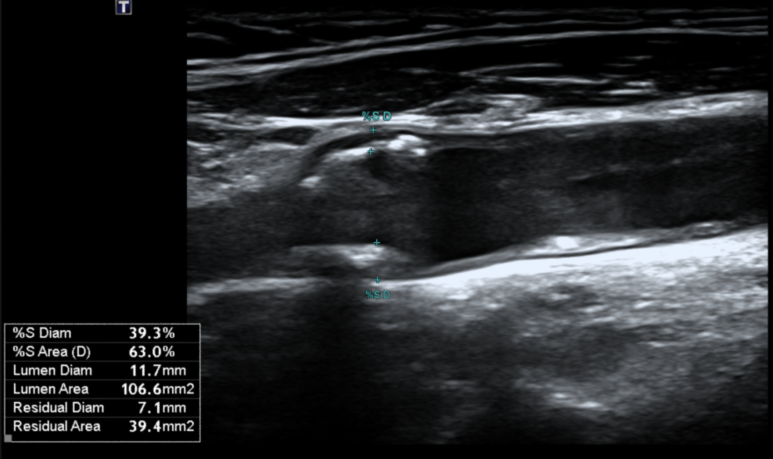

고혈압 환자분의 경동맥 초음파 결과

고혈압 환자 10명 중 3~4명은 합병증이 생기고 나서야 진단받는다고 알려져 있습니다.

그만큼 조기 발견과 치료가 가장 중요합니다.